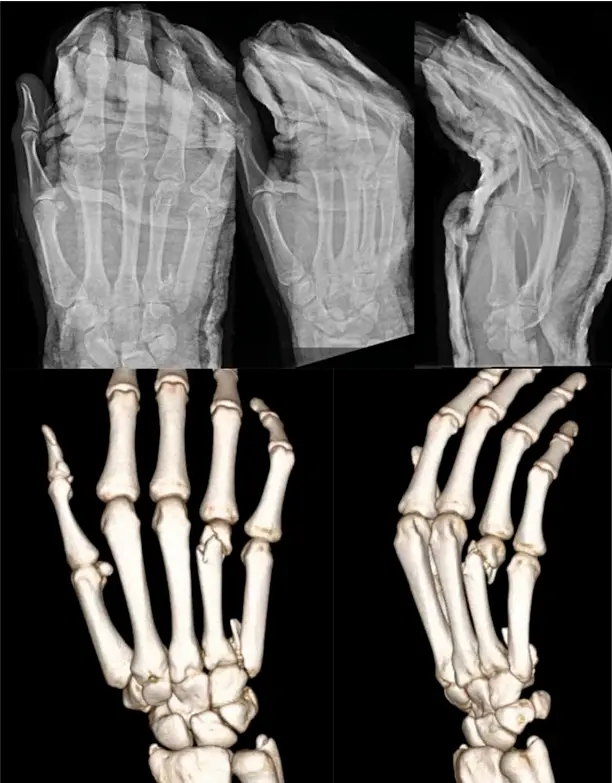

2. Intramedullary Screw Fixation for Metacarpal Head Fractures

Intramedullary Screw Fixation.png

Intramedullary Screw Fixation 2.png

Intramedullary Screw Fixation 3.png

5. Intramedullary Screw Fixation for Metacarpal Neck Fractures

6. Intramedullary Screw Fixation for Multiple Spiral Metacarpal Shaft Fractures